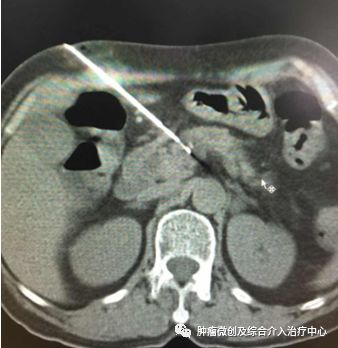

碘125粒子植入后CT